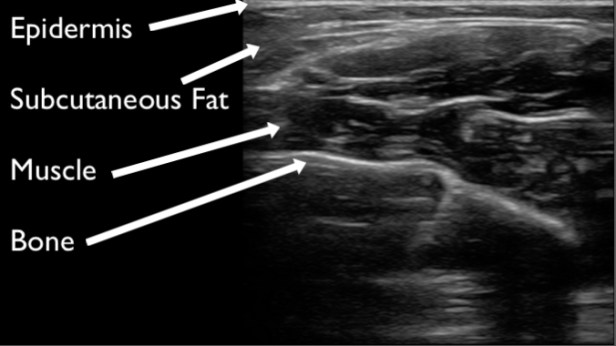

Figure 1 demonstrates normal appearing layers of soft tissue, fascia, muscle and bone. In general, the epidermis, fascia, and bone are hyperechoic compared to subcutaneous fat and muscle (which are hypoechoic). Bone will typically produce a clean shadow. Figure 2 demonstrates normal bony cortex in a long axis with shadow below. Muscle in a short axis is mostly hypoechoic with a few hyperechoic portions (Figure 3). In the long axis you can appreciate muscle fiber striations (Figure 4). Tendon in a long axis appears as a thin, well demarcated structure with striated fibers (Figure 5). Figure 6 demonstrates the principle of anisotropy, which is most apparent when imaging tendons and muscles. Muscle and tendon may appear focally hypoechoic depending on the angle of the transducer, but this is artefactual and will disappear with further interrogation. Figure 7 demonstrates a normal shoulder joint with no anechoic effusion and normal articulation of the glenoid and the humeral head.

Figure 1. Normal soft tissue, muscle, fascia, and bone layers on gray scale ultrasound.